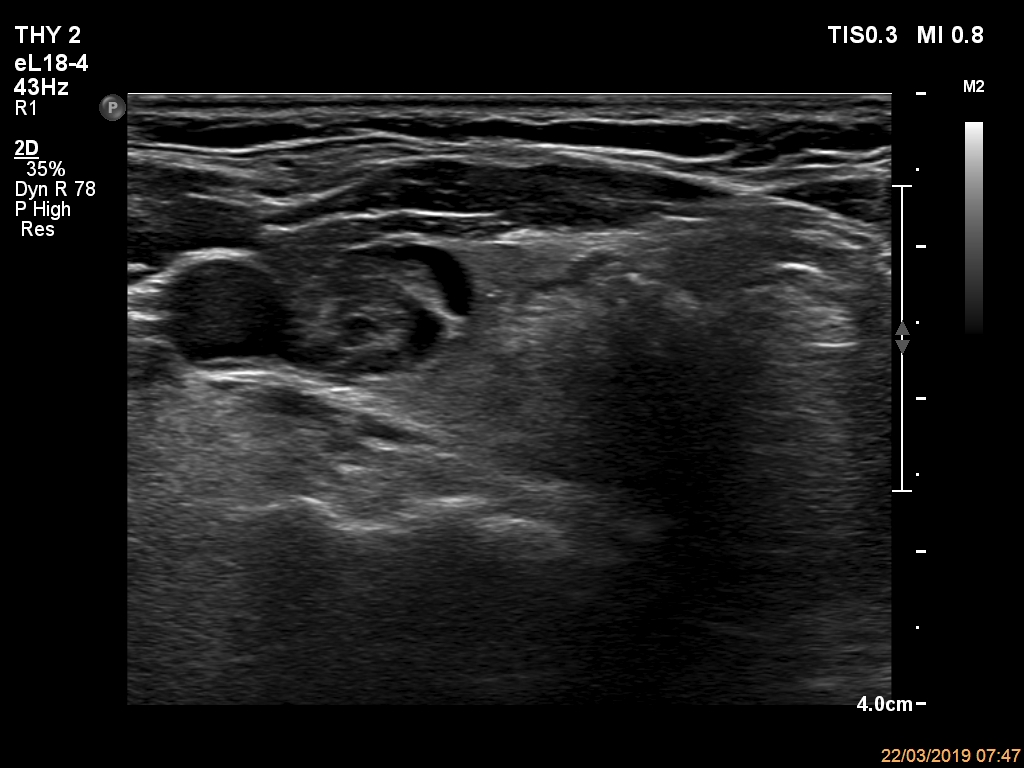

Ultrasonography. The thyroid was echonormal and had multiple nodules. The only lesion of a possible oncological importance was in the left lobe. It was hypoechoic. The dimensions were 16x14x23 mm (width, depth, length, respectively). The lower border presented an undulation which was caused by another, hyperechoic nodule. The nodule presented a predominant perinodular blood flow and had an average rigidity on elastography.

The nodule in the left lobe illustrates non-pathological form of lobulated margins.